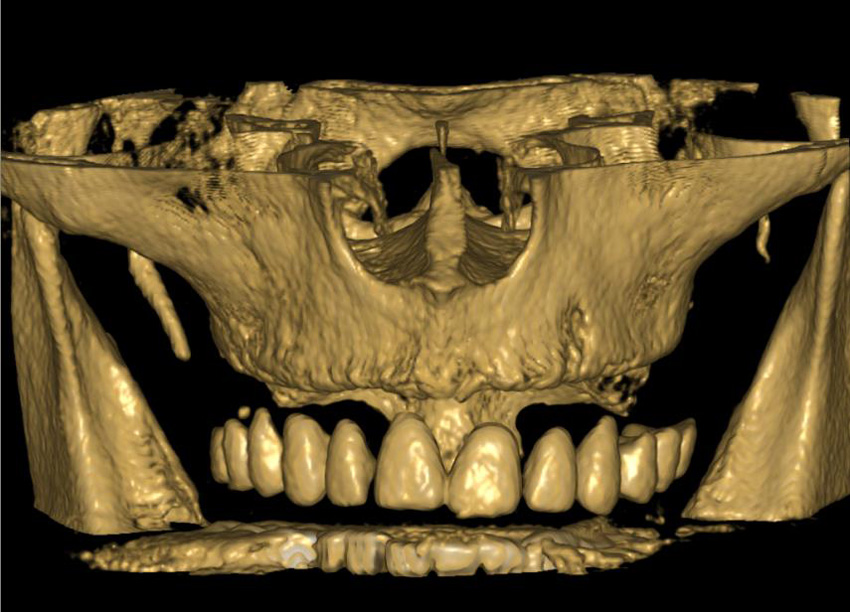

Zubní implantát, tedy v podstatě umělý zubní kořen, se zavádí do čelistní kosti a díky speciálně upravenému povrchu implantátu po určité době pevně přilne ke kosti. Tím dojde ke „vhojení implantátu“ (používá se označení osseointegrace),

který se stane pevnou součástí kosti a je připraven k zatížení korunkou. Pro úspěšnou osseintegraci je však nutné přesné umístění implantátu do čelistní kosti, proto by mělo vždy každému zavedení implantátu předcházet dokonalé klinické a 3D

rentgenologické vyšetření. Na základě těchto vyšetření je ve spolupráci se zubní laboratoří zhotoven finální chirurgický i protetický plán ošetření. Tento plán zahrnuje přesnou pozici, plánovanou hloubku i sklon implantátů a zhotovení chirurgické

šablony pro řízenou nebo navigovanou implantaci pro perfektní finální funkční i estetický výsledek. Navigovaná/řízená implantologie operatérovi pomáhá vedením vrtáčku do kosti do přesné pozice, aby nedošlo k poranění pacienta, nepředvídatelným

Principem řízené navigace pomocí chirurgických šablon je pasivní vedení zahlubovacích a rozšiřovacích vrtáčků do čelistní kosti na základě předem naplánované přesné pozice, směru, sklonu a hloubce jednoho nebo více implantátů.

Chirurgicko-protetický plán vychází z 3D rentgenu čelisti, otisku zubů a dásně (scanu zubů a dásně) a finálního návrhu protetické náhrady. Na základě těchto dat je v plánovacím softwaru coDiagnostiX vytvořena chirurgická šablona,